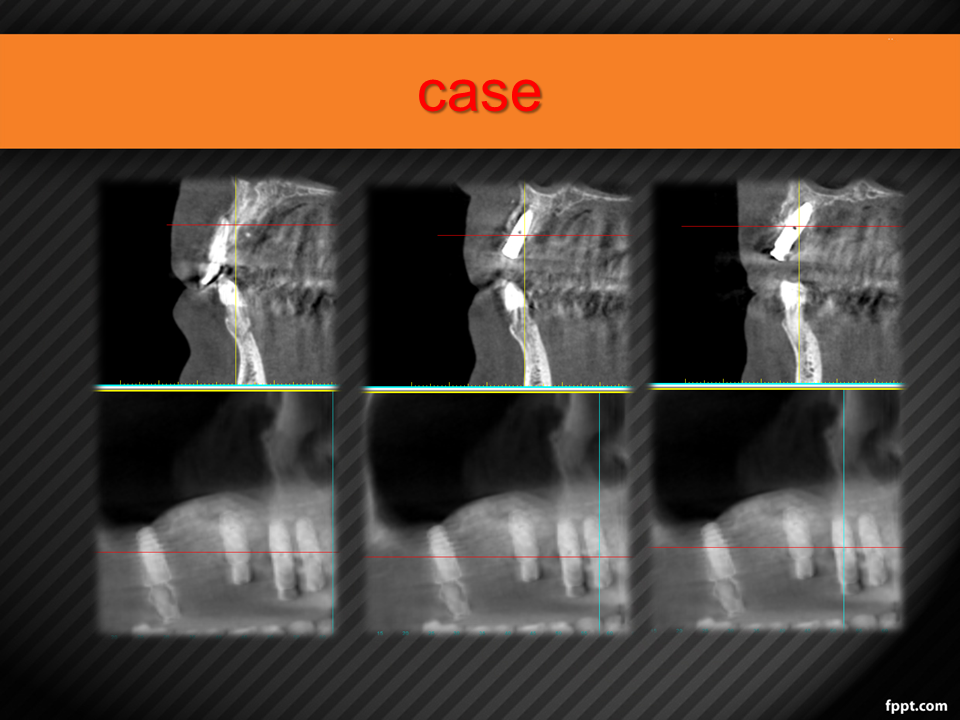

Vertical Alveolar Ridge Augmentation with 3D-Printed Titanium Mesh (30.10.2021)

Case report on vertical bone augmentation using a customized 3D-printed titanium mesh in a complex clinical scenario with prior implant failures. Includes surgical planning, techniques, complications, and an invitation for multicenter research collaboration. Presented by Dr. Levon Galstyan at AAOMFS.